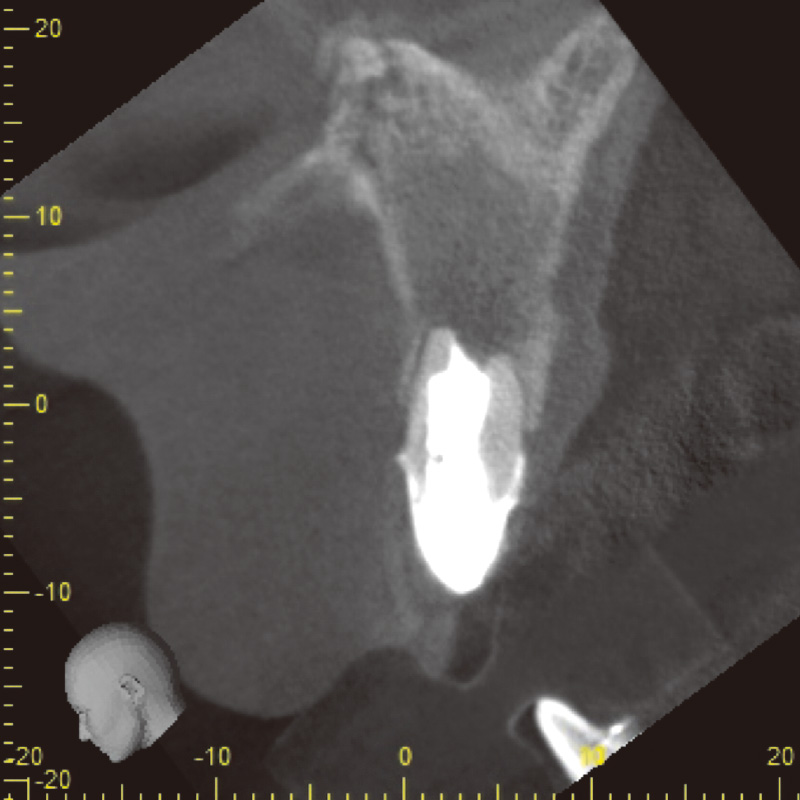

62歳女性で、₅に咬合痛があり近医にてメタルクラウンとメタルポストコアを除去したが、痛みと違和感が継続しているとのことで来院した。自発痛(-)咬合痛(+)・打診痛(+)・根尖部腫脹(-)根尖圧痛(軽度)であり、デンタルでは根尖部透過像・根尖孔外に突き出た根管充填材を認めた(症例2-1)。CBCTにおいても根尖孔外に突き出した根管充填材を認めた(症例2-2)。

症例2-2 初診時CBCT画像![[写真] ガッタパーチャ除去](/academic/dentalmagazine/wp-content/uploads/sites/2/2025/11/195-6_photo09.jpg)